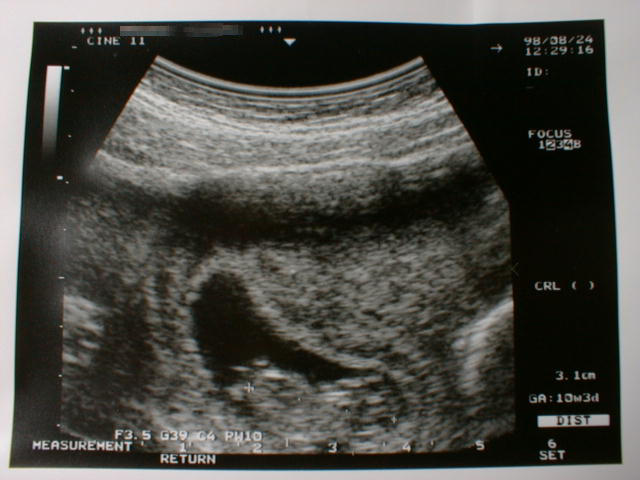

第10週に入った胎児の写真です。

(大きさは、3.1cm)